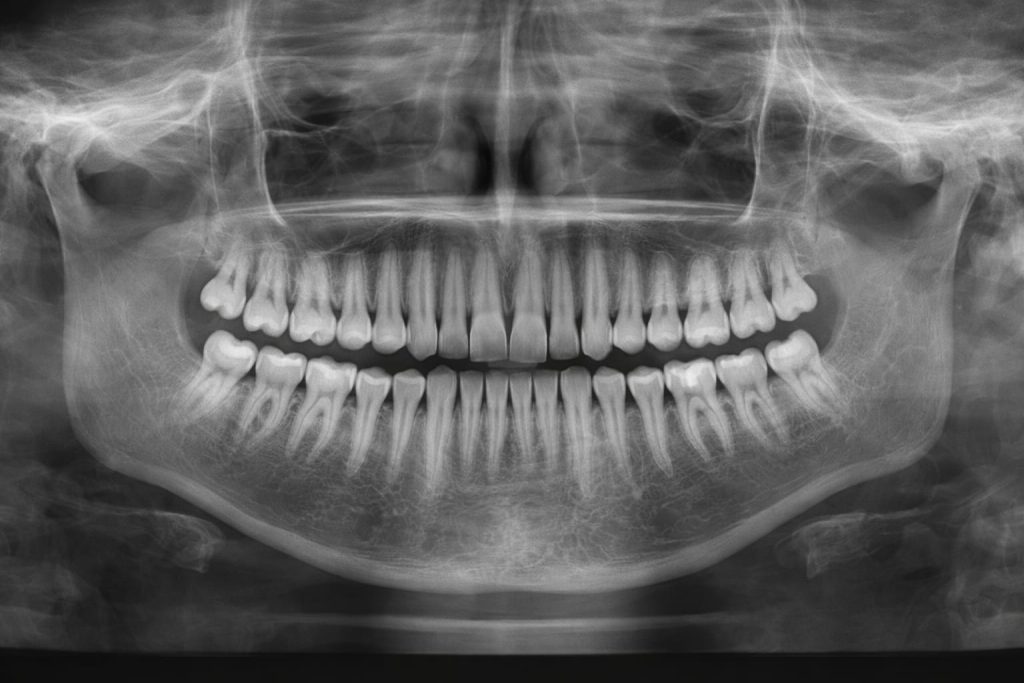

A radiografia panorâmica ou ortopantomografia é um exame diagnóstico que permite obter uma imagem completa da boca numa única captura.

Através da ortopantomografia, conseguimos observar dentes, ossos maxilares, articulações temporomandibulares e estruturas adjacentes de forma rápida e precisa.

A ortopantomografia permite detetar:

• Dentes retidos ou inclusos (como os dentes do siso)

• Infeções ou quistos

• Perda óssea

• Problemas na articulação temporomandibular (ATM)

• Alterações no desenvolvimento dentário

• Planeamento para implantes, ortodontia ou cirurgias

É uma ferramenta essencial para ter uma visão global da saúde oral.